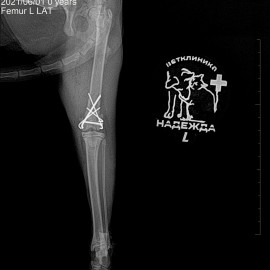

После полученной травмы от удара, кошка перестала вставать на заднюю левую лапу. После осмотра и рентгенологического исследования был поставлен диагноз: перелом левого бедра. 31.12.2021 была проведена операция: остеосинтез левого бедра.

Снимки 2-3 после операции.